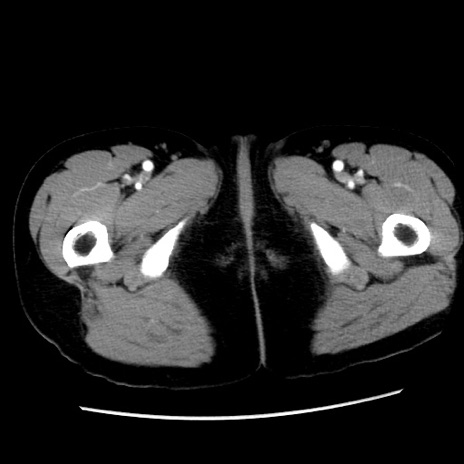

症例10(横断像)

【症例】 50歳代女性

【主訴】 腹痛

【現病歴】前日生レバーを食べた。今朝に排便あり。 昼前に突然発症の腹痛を生じ、当院救急外来を受診した。

【既往歴】 子宮筋腫にてで子宮全摘後

【身体所見】 意識清明、腹部:平坦、軟、下腹部やや左を中心に圧痛・反跳痛あり、筋性防御あり

【データ】WBC 7800、CRP 0.07